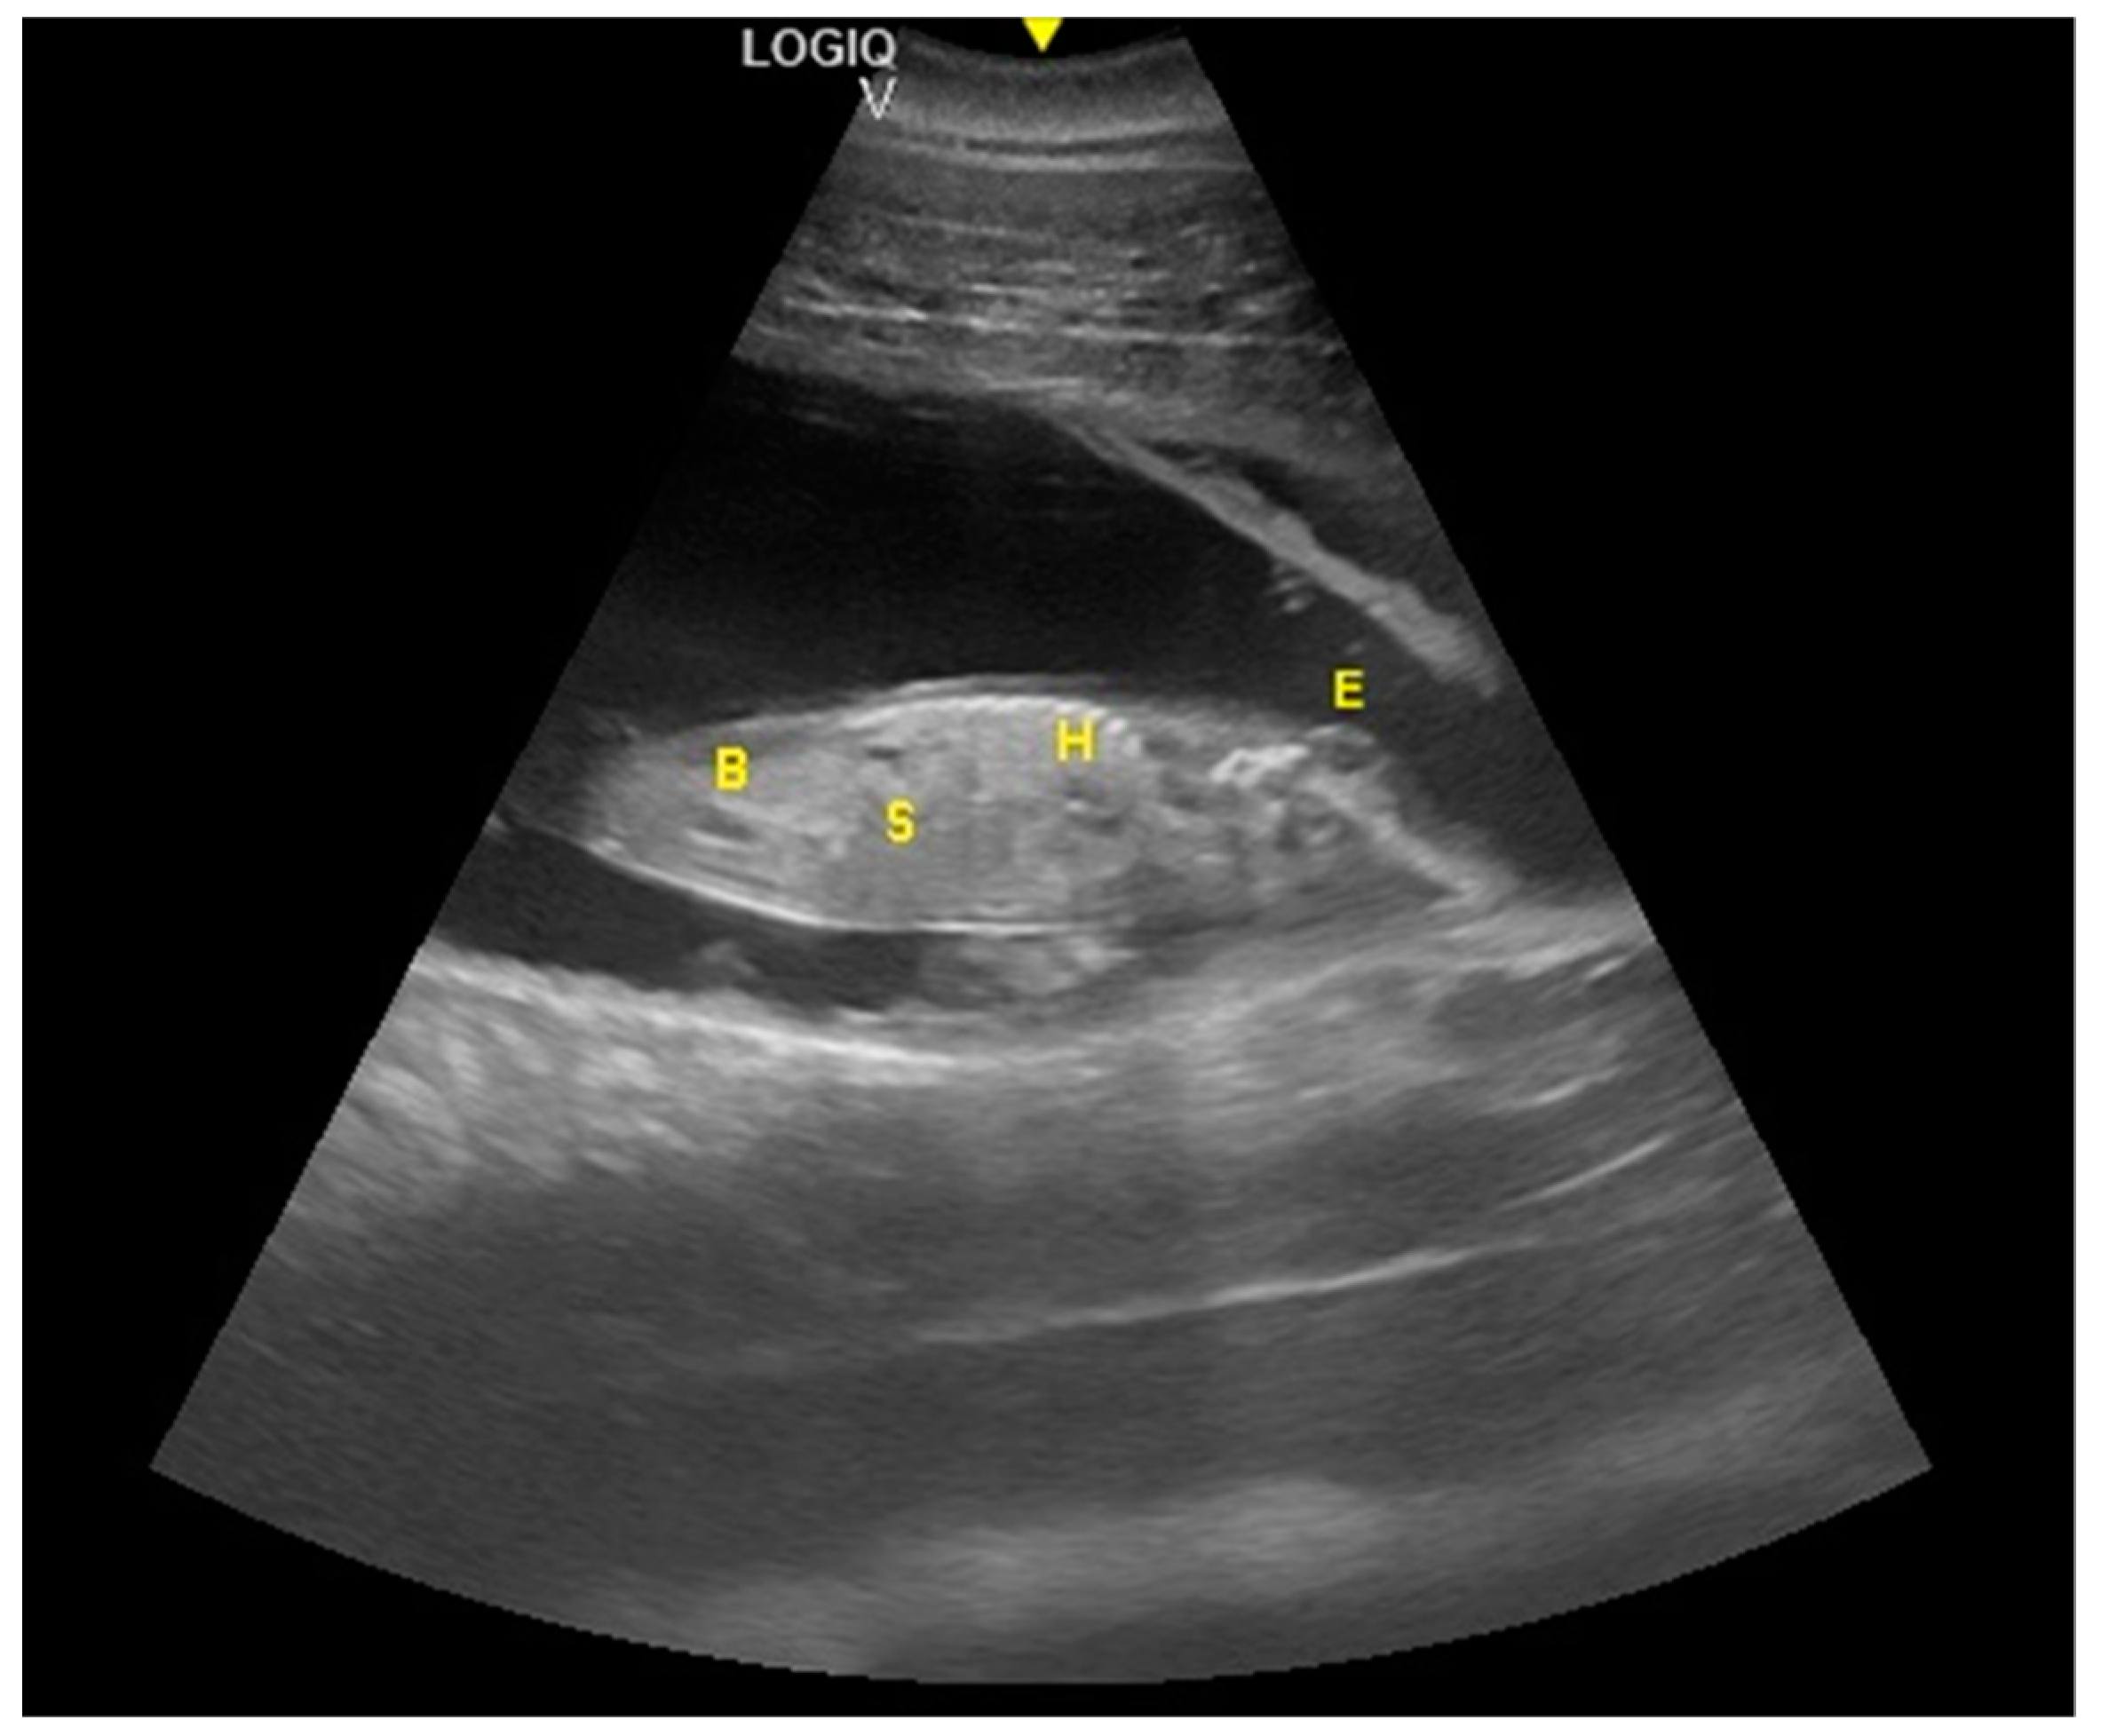

The distinction between head and trunk was visible starting from 68 ± 5 days after ovulation. From the 216 ± 5 days of gestation, measurements started to be hard to realize with accuracy. In fact, in the evaluations after this last period, the position/orientation of the fetus and its size meant that it was not possible to take reliable measurements thereafter. Starting from 68 ± 5 days after ovulation, the embryonic cardiac mechanisms were displayed as a point of maximum fluctuation of the echoes. The heart rate was measured because the cardiac mechanics became visible and remained constant between 155 and 198 bpm until the ninth month of pregnancy (Figure 3). During the last 3 months, it stabilized at 140 bpm, to reach 85 ± 5 bpm in the last 2 weeks of gestation. The first abdominal organs to be visualized were the stomach and the urinary bladder (98 ± 3 and 110 ± 2 days of gestation, respectively), which appeared as distinct and anechoic cavities. It was also possible to recognize the eye as an anechoic cavitary structure (Figure 4).

Figure 4.

Fetal stomach (S) and fetal urinary bladder (B) were the first abdominal organs to be visualized, and appeared as distinct and anechoic cavities. The heart was recognizable as an anechoic cavity (H) and the embryonic cardiac mechanics were displayed as a point of maximum fluctuation of the echoes. The eye appeared as an anechoic cavitary structure (E).

The distinction between thorax and abdomen and, thus, the presence of the diaphragm, was seen at 92 ± 5 days of gestation. A clear distinction between lungs and liver was identified at 112 ± 5 days, whereas the ribs were visible at 153 ± 5 days. At 167 ± 3 days of gestation, the dorsal fin was visible as a hyper-echoic triangular structure in the dorsal portion of the trunk. During the same period, it was possible to identify the teeth. Even if the umbilical cord was easily guessed previously (as shown in Figure 3) from the 119 ± 6 day of gestation, it was clear as a hyper-echoic cordoniform structure, and it was important to evaluate the internal vascular components and the absence of knots or torsions until the birth (Figure 5). Furthermore, it was possible to notice, between the 149th day and the 230th day of gestation, that the eye was open, the lens was visible, and eyelid movements were also detectable (Figure 6).